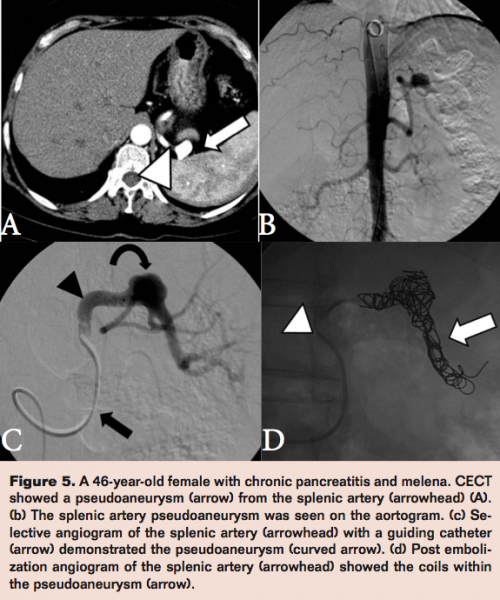

In order to avoid this, the sandwich technique embolizes the parent artery both distally and proximally in relation to the aneurysmal neck. A patient with a splenic artery pseudoaneurysm due to chronic pancreatitis was treated in this way using embolization coils (Figure 5).

63 patients were included in this study. Males were more common than females (4.7:1) and more than half of the patients were in the 30 to 60 year age group. The most common symptoms were abdominal pain, melena, and hematemesis (Figure 1A). Pancreatitis (30%), surgery (22%), infection (12%), and trauma (12%) were the most common causes (Figure 1B). The most common locations were the hepatic artery (41%) and the splenic artery (27%; Figure 1C). The most common endovascular techniques used were proximal coil embolization (41%) and the sandwich technique of coil embolization (27%; Figure 1D). A high success rate of 92% was seen overall. Two patients underwent successful embolization but died due to causes unrelated to the bleeding. Rebleeding occurred in four patients (8%). Two patients underwent repeat embolization and one underwent surgery with good results. A repeat angiogram did not reveal a source of bleed in the fourth patient and he continued to bleed and died despite blood transfusions and inotropic supports. A few complications were seen. Inadvertent dislodgement of an embolization coil into the parent hepatic artery was seen in one patient. A pseudoaneurysm of the hepatic artery ruptured during the coil embolization and was treated with hepatic artery embolization. Subintimal dissection of a gastroduodenal artery occurred and was treated by balloon angioplasty. Cystic necrosis of the spleen was seen on a follow-up CT scan, which was a result of embolization of a splenic pseudoaneurysm with Histacryl n-butyl cyanoacrylate glue (B. Braun).